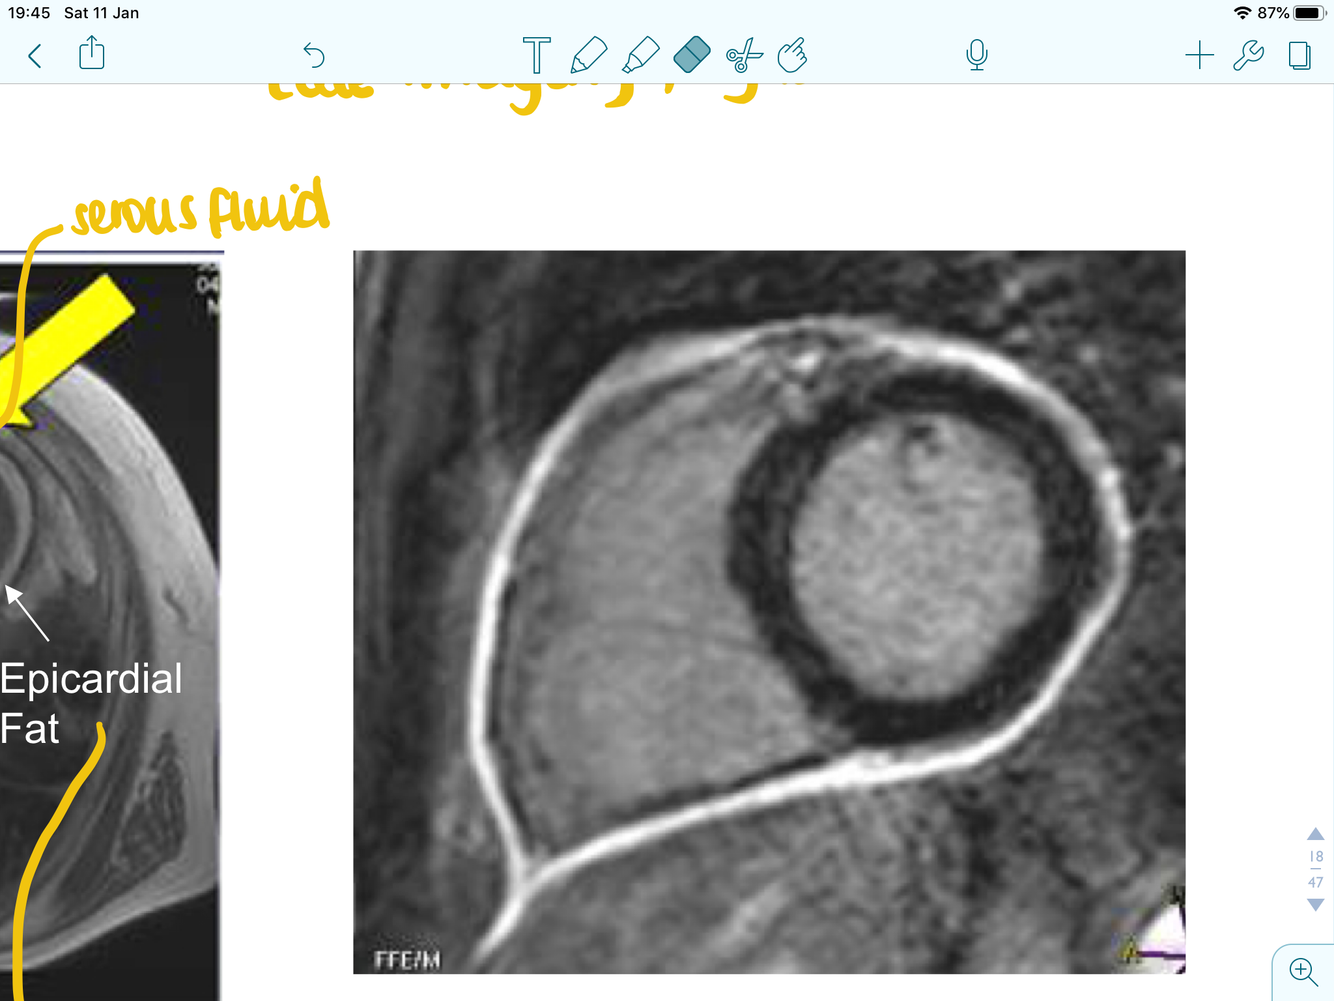

what doe this image show and what type of test is it?

MRI